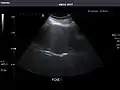

Kidneys: Right and left kidneys measure 11.5 cm and 12 cm in length respectively. No hydronephrosis. Small left lower pole kidney cyst.

Right kidney